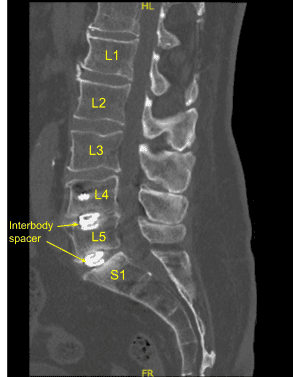

This patient previously underwent L4 to S1 minimally invasive transforaminal lumbar interbody fusion. They did well and recovered, however subsequently developed recurrence of their low back pain, had various injections and nonsurgical treatments including a sacroiliac joint fusion.

However, their back pain only worsened. Imaging showed loosening of bilateral pedicle screws and signs of pseudarthrosis. Surgery was recommended to stabilize the lumbar spine. The risks, benefits, alternatives and potential complications of the surgery were explained to them.

The patient was draped sterilely. CT scan was obtained, and data was transferred to the neuronavigation computer. Neuronavigation techniques were used to reposition and replace bilateral sacral screws which were upsized both in diameter and length until tight.

Additional CT scans were performed showing correct positioning of all the pedicle screw hardware. Neuromonitoring signals were stable. Next, we decorticated bilateral transverse processes and facet joints including sacral ala from L4 to S1 bilaterally with electric high-speed drill for the arthrodesis. The wound was irrigated copiously.